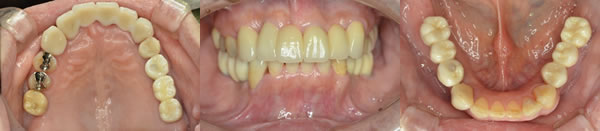

■治療後

患者さんは美味しく食事ができ、人前でも笑うことが出来るようになったと大変満足していました。食べる喜びを取り戻すことができ、美味しく食事を摂ることは何事にも替えられないものがあると痛感されていました。